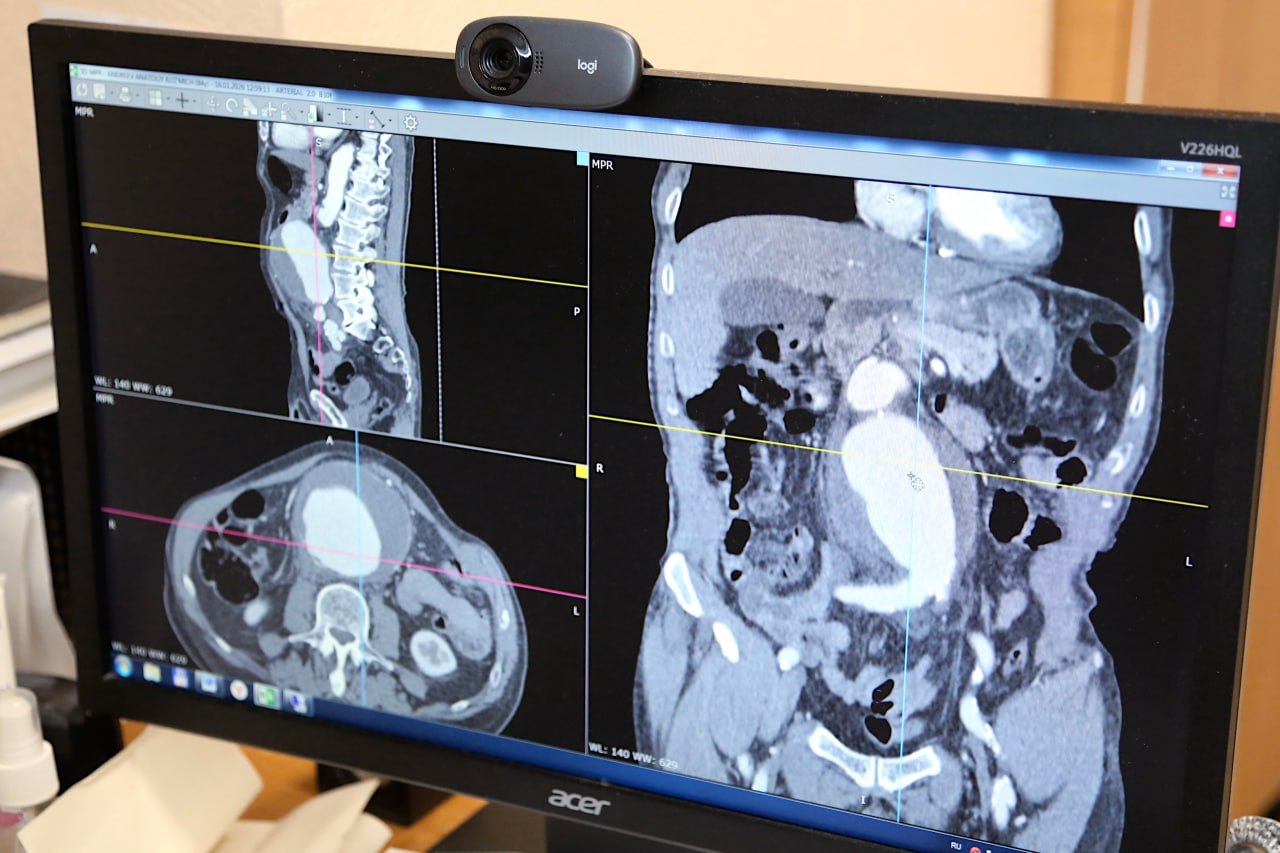

О спасении жизни новгородца с аневризмой аорты, благодаря диагностике и взаимодействию врачей трех клиник рассказали в минздраве Новгородской области.

После уборки снега 54-летний мужчина почувствовал себя плохо и потерял сознание. Бригада скорой медицинской помощи доставила его в клинику № 1 Центральной городской клинической больницы Великого Новгорода.

При осмотре жалобы и симптомы в виде слишком низкого давления, бледности и влажности кожи насторожили кардиолога Екатерину Щербакову и реаниматолога Алису Вагнер. Хотя анализы были в пределах нормы, врачи решили провести дополнительные исследования.

Компьютерная томография с контрастом и эхокардиограмма сердца показали аневризму грудного отдела аорты – это серьезная патология, которая заключается в расширении или выпячивании стенки крупнейшей артерии в грудной клетке. Такое состояние часто протекает бессимптомно, но может привести к смертельно опасному разрыву сосуда.

Мужчину немедленно перевели в реанимационное отделение, для консультации связались со специалистами Новгородской областной клинической больницы. После осмотра пациента врач сосудистый хирург Тимур Гасайниев провел телемедицинскую консультацию с ведущими специалистами Национального медицинского исследовательского центра имени В.А. Алмазова.

Пациенту требовалась пластическая коррекция корня аорты – вид оперативного вмешательства, который выполняется только федеральными медицинскими центрами. Поэтому специалисты приняли решение о срочном переводе мужчины санавиацией в Санкт-Петербург.

«Операция прошла успешно, новгородец быстро пошел на поправку благодаря своевременной диагностике и эффективному взаимодействию врачей городской, областной и федеральной клиник», — отметили в сообщении